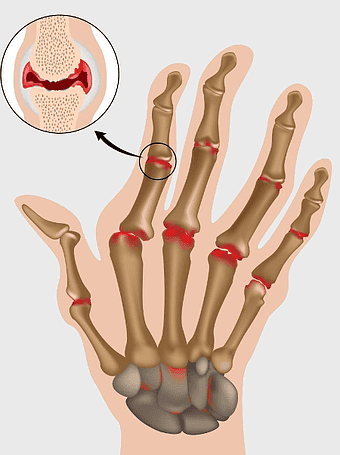

450x602px

rheumatoid arthritis hand symptoms, adalimumab for joint pain, chronic arthritis therapy, hand joint inflammation, autoimmune disease treatment, medical illustration of arthritis, rheumatology patient care -